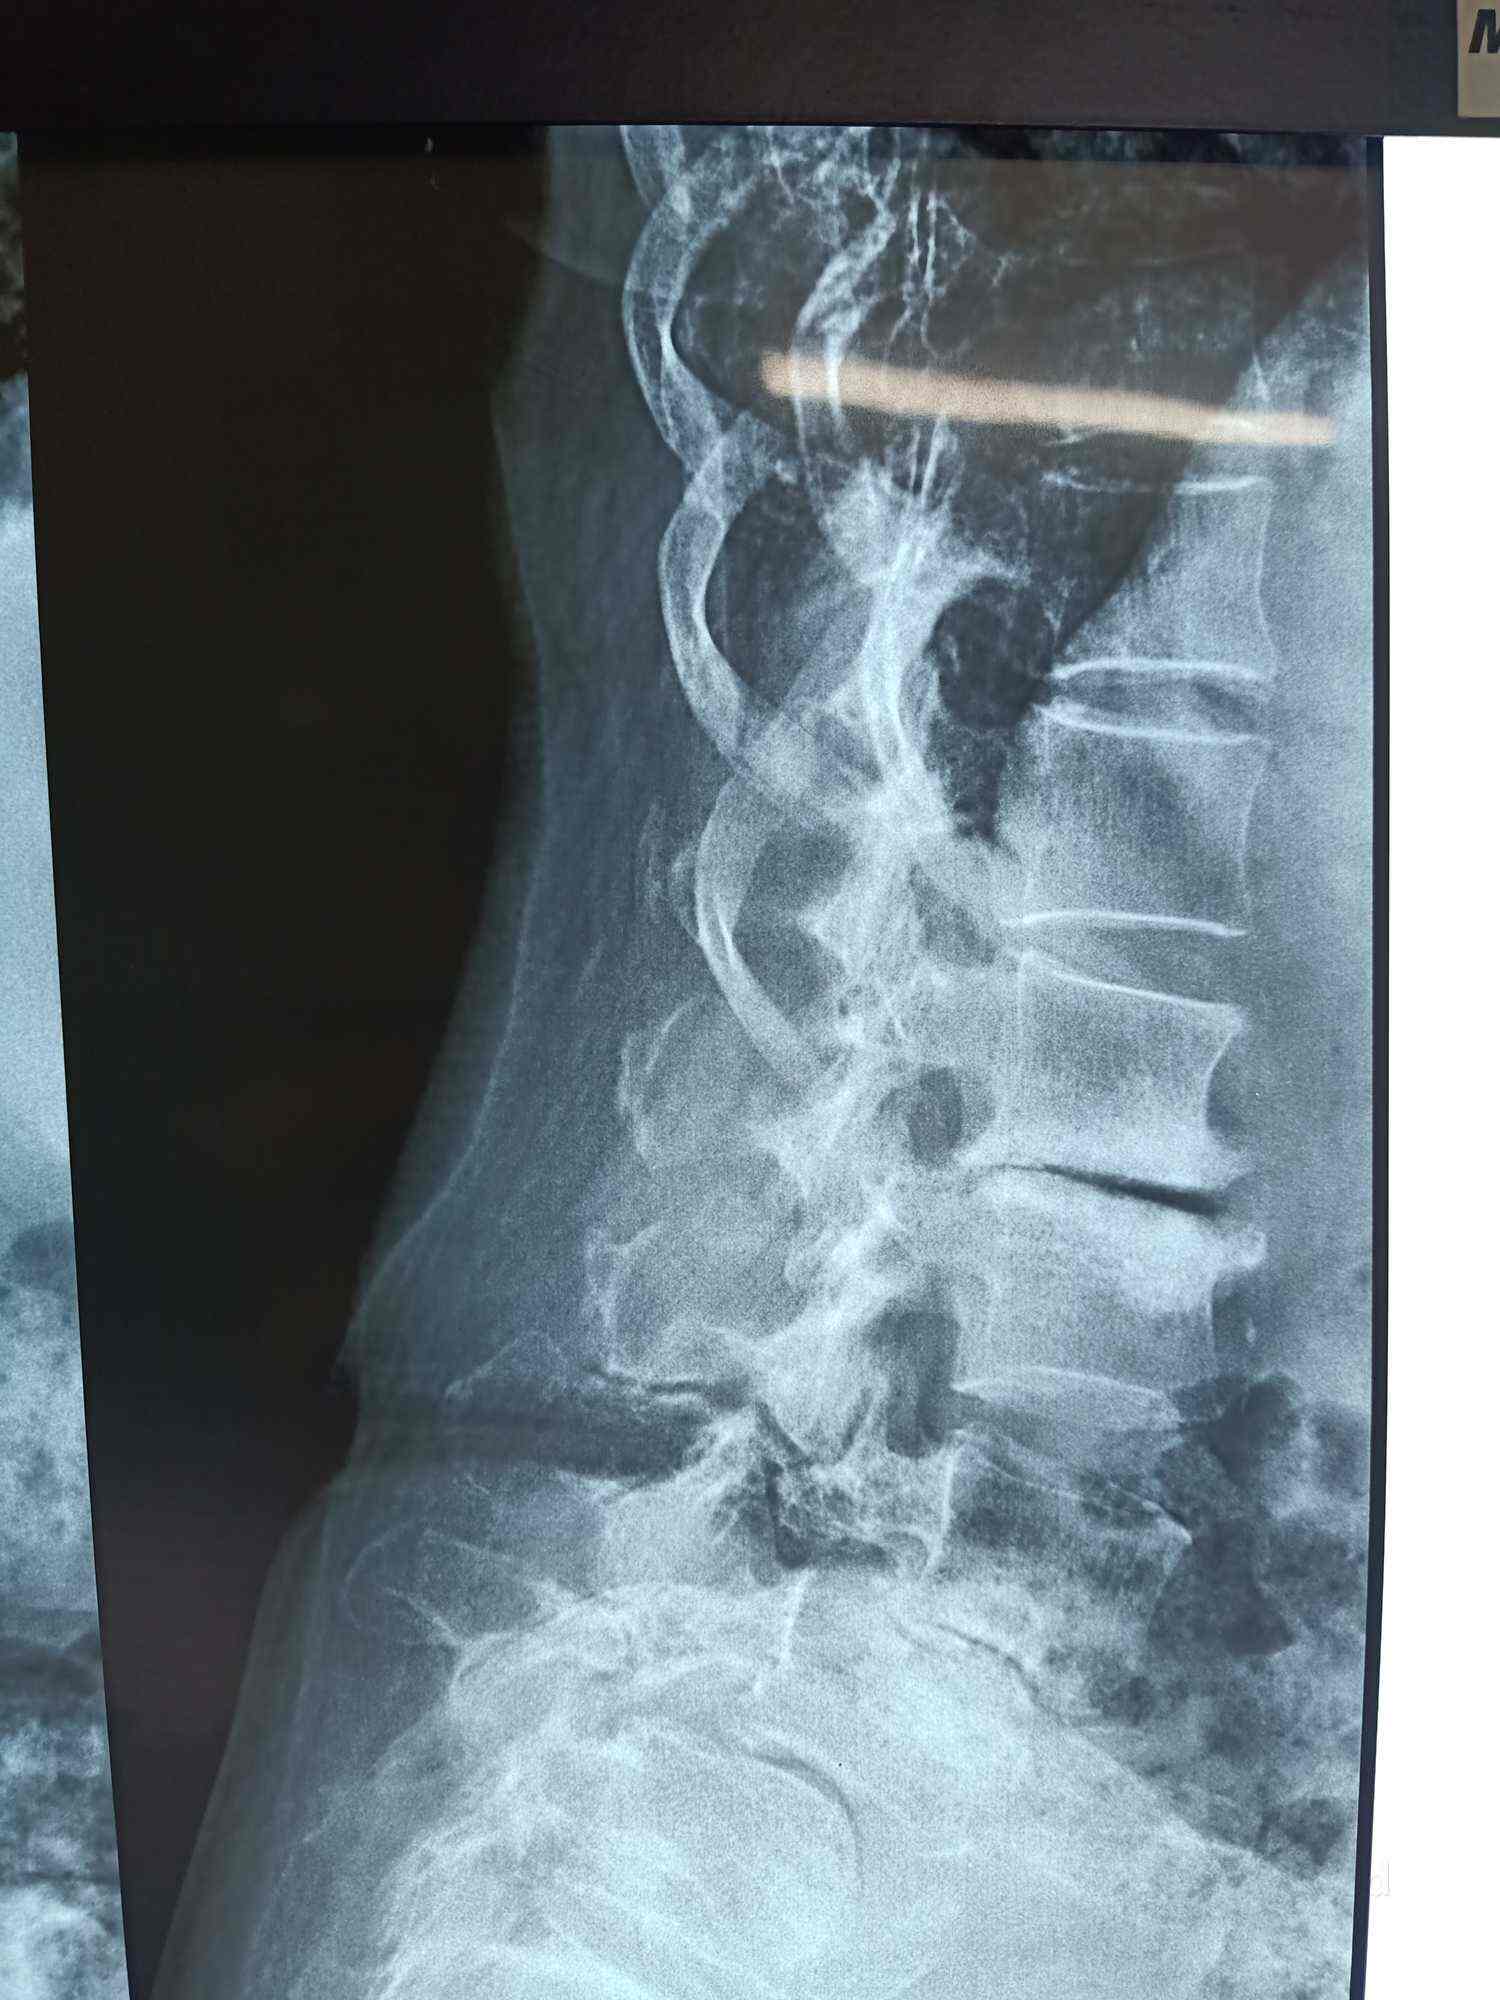

Dr Rohit Rao Pushkar Lucknow

Dr Rohit Rao Pushkar Lucknow - Vrach, uslugi uhoda za kozhey.